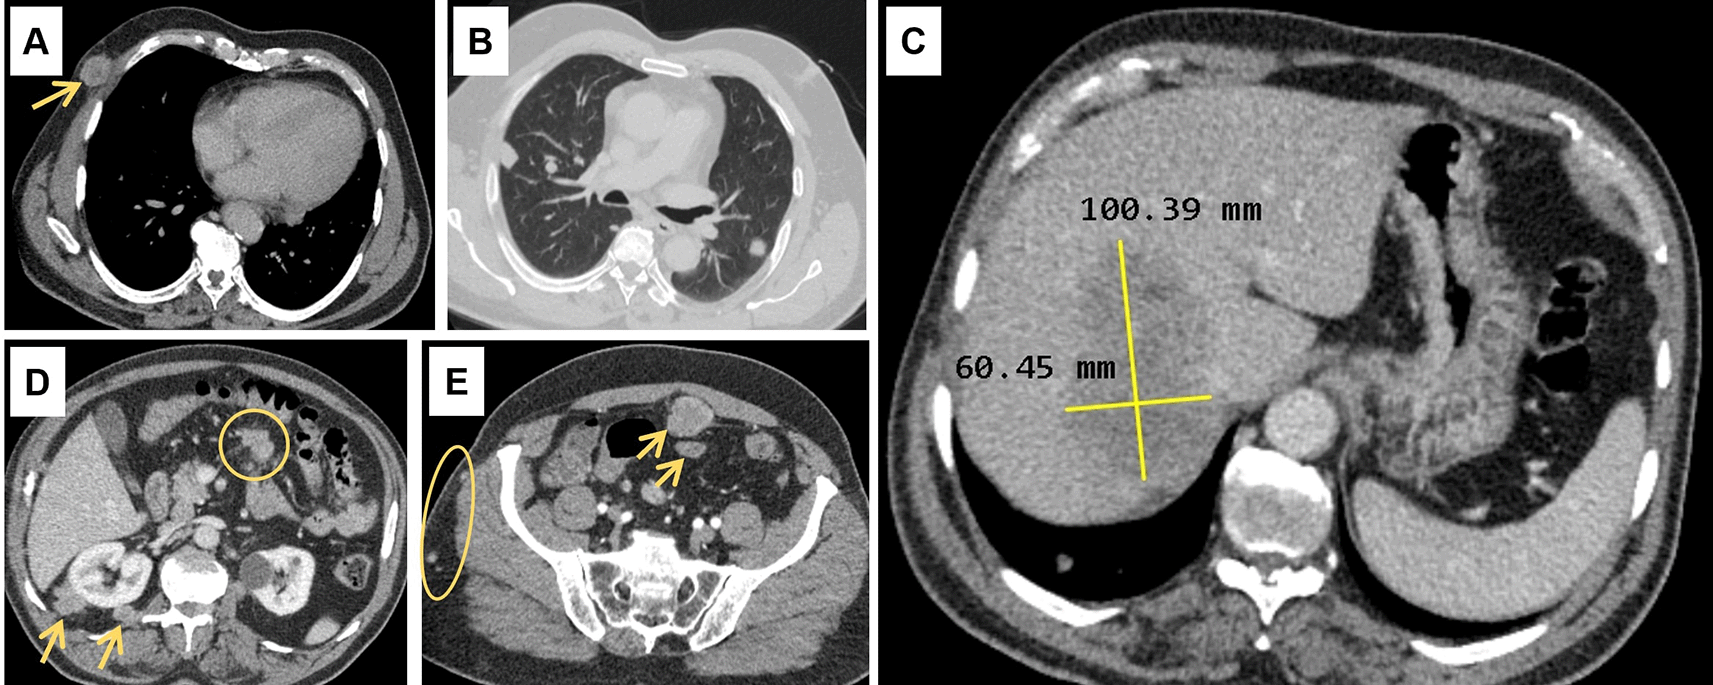

Abdominal ultrasound (US) showed a non-dysmorphic liver with a heterogenous lobulated hypoechoic mass, vascularised on Doppler, measuring 83 × 60 mm, associated with omental adipose tissue nodule of 37 mm, sharing the same characteristics. On the CT scan ( Figure 1), the hepatic mass was isodense, poorly defined, spanning segments V, VII and VIII, showing weak enhancement with contrast, measuring 100 × 60 mm. There were also multiple scattered tissue masses enhanced with contrast, located in the peritoneum, in the retroperitoneum, and sub-peritoneal, as well as in the left adrenal gland. The pancreas was normal. Plus, multiple solid pulmonary nodules were observed, involving all segments, alongside mediastinal and abdominal lymphadenopathies.

(A): Subcutaneous soft tissue nodule of the anterior right thoracic wall (arrow). (B): Bilateral pulmonary nodules. (C): Hypodense hepatic mass in the right lobe on the portal phase, measuring 100 × 60 millimetres. (D): Intraperitoneal adenomegalies (circle) and heterogeneous nodules in the right perirenal retroperitoneal region. (E): Heterogeneous peritoneal nodules (arrows) and small subcutaneous soft tissue nodules in the right lateral abdominal wall (circle).